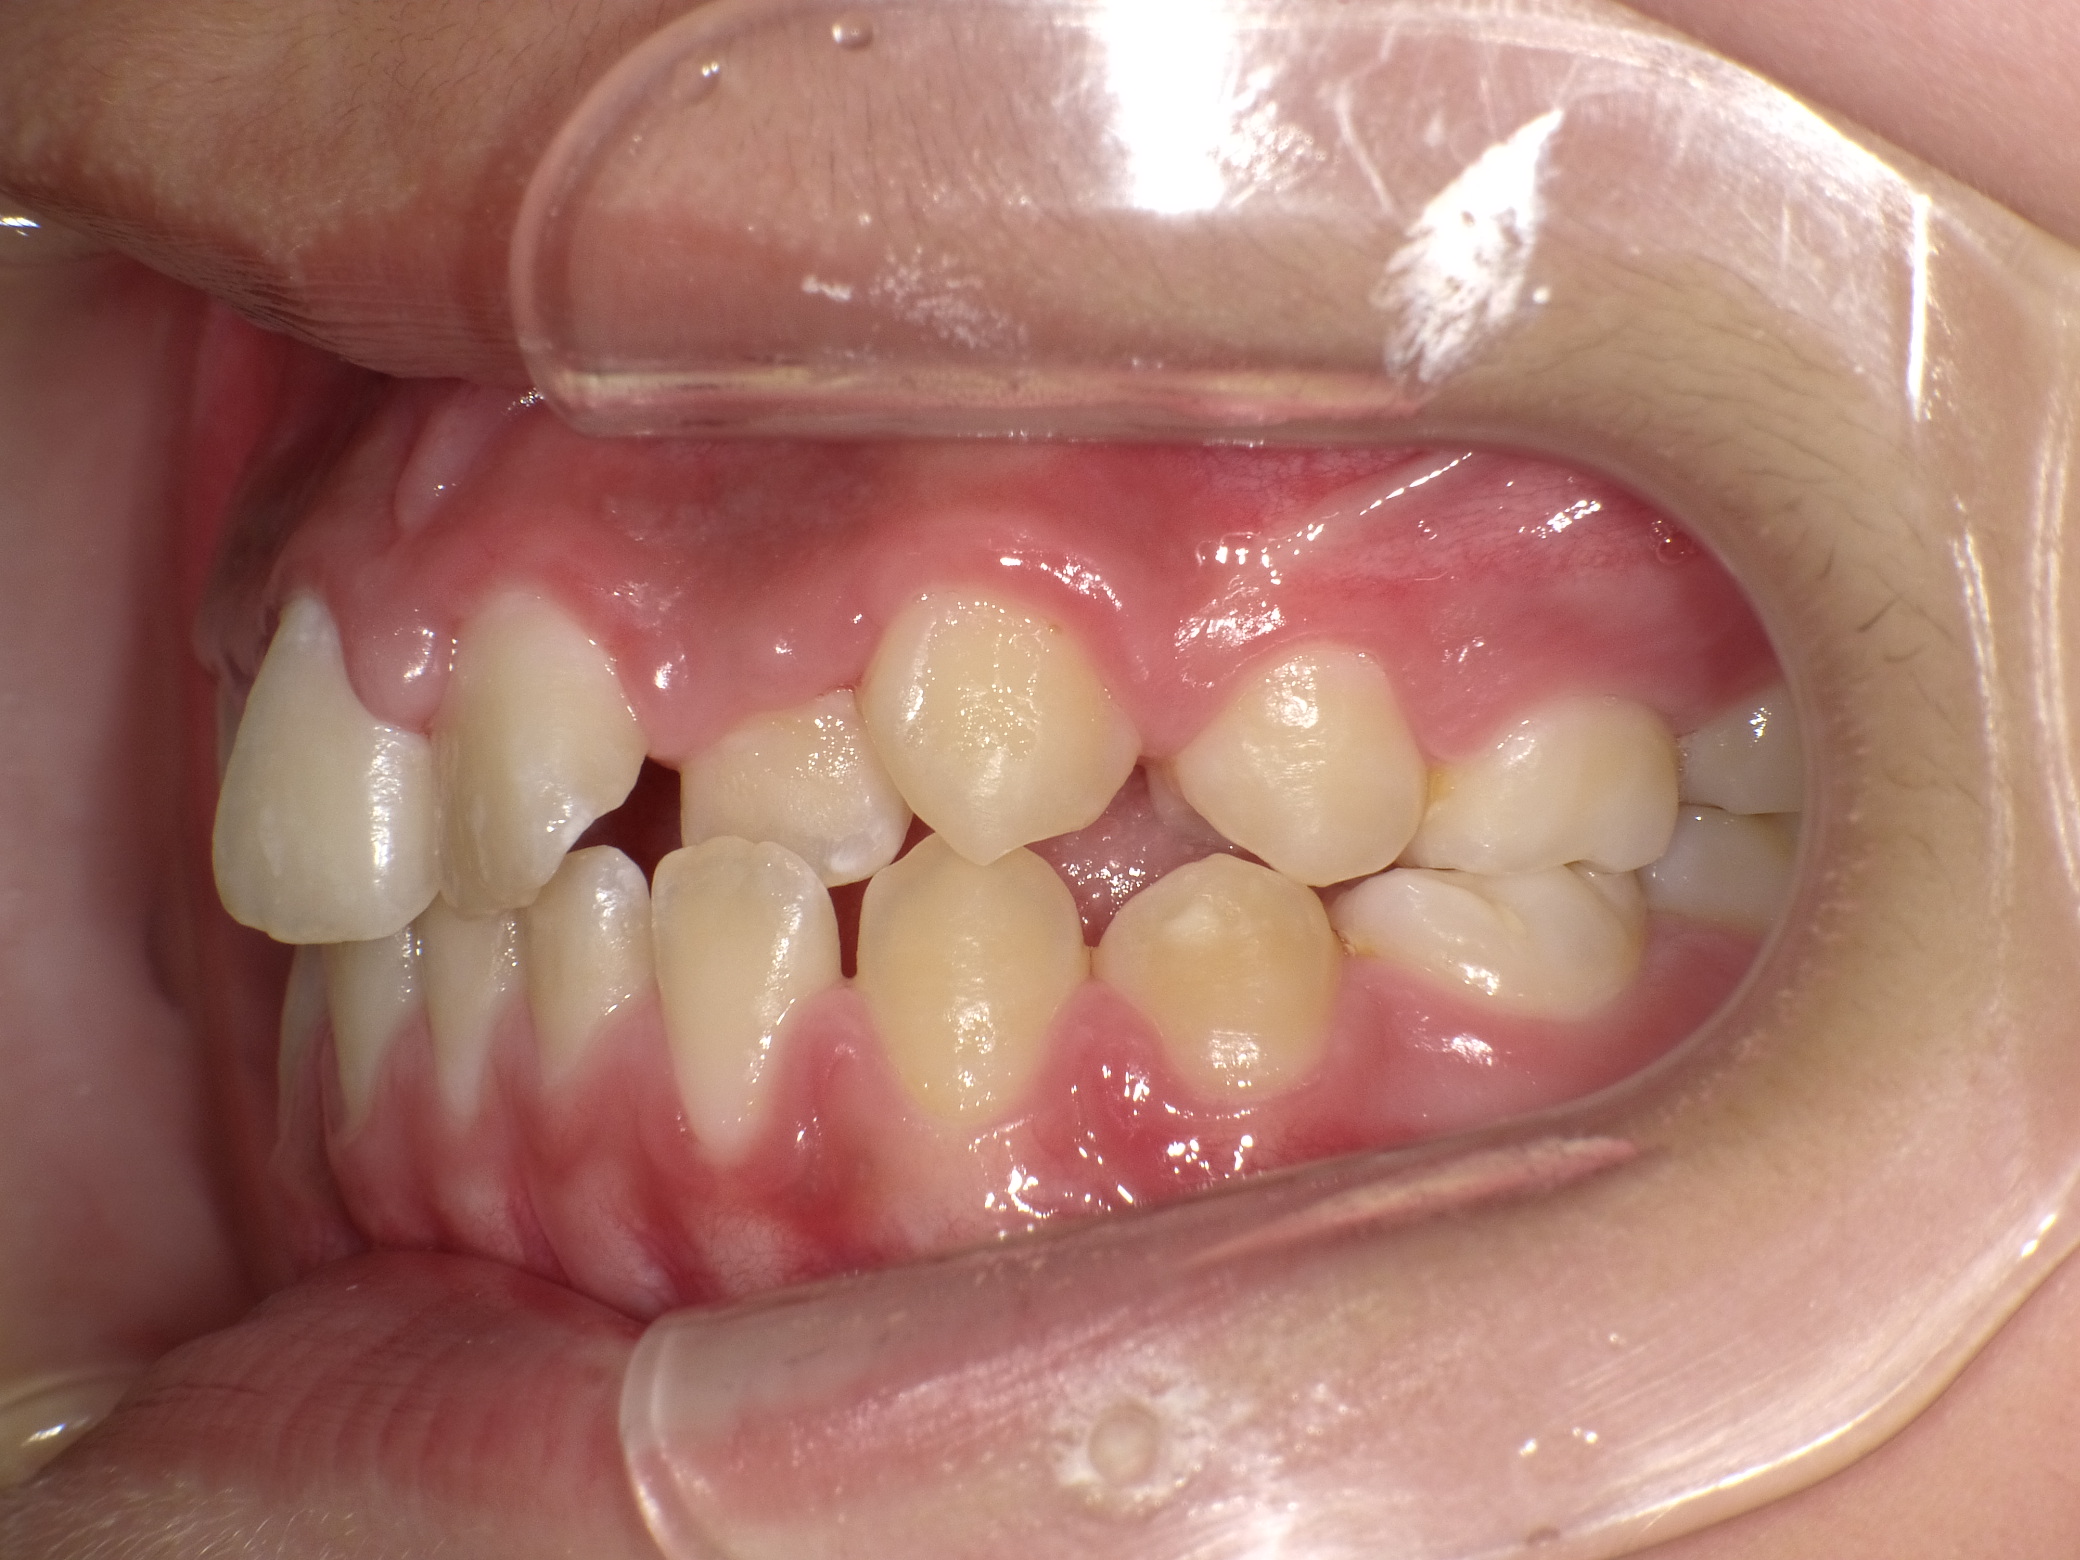

【小学生】マイオブレース矯正 受け口を改善 ①

小学生で開始

マイオブレース

受け口

1期治療のみで改善

Before

After

治療期間

1年11カ月年

治療開始

10歳

種類

マイオブレース矯正

使用装置

機能矯正装置

コメント

毎日装置の装着と MFT 口腔筋機能療法 に取り組んでくれたためスムーズに終わりました。

上顎前歯の並びをもう少し別の装置で改善することも提案しましたが、本人、保護者の方ともに

今の歯並びで満足しているということだったのでこれで終了しています。

MFTを頑張ってくれたため、お口の筋肉バランスもよく、後戻りもしていません。